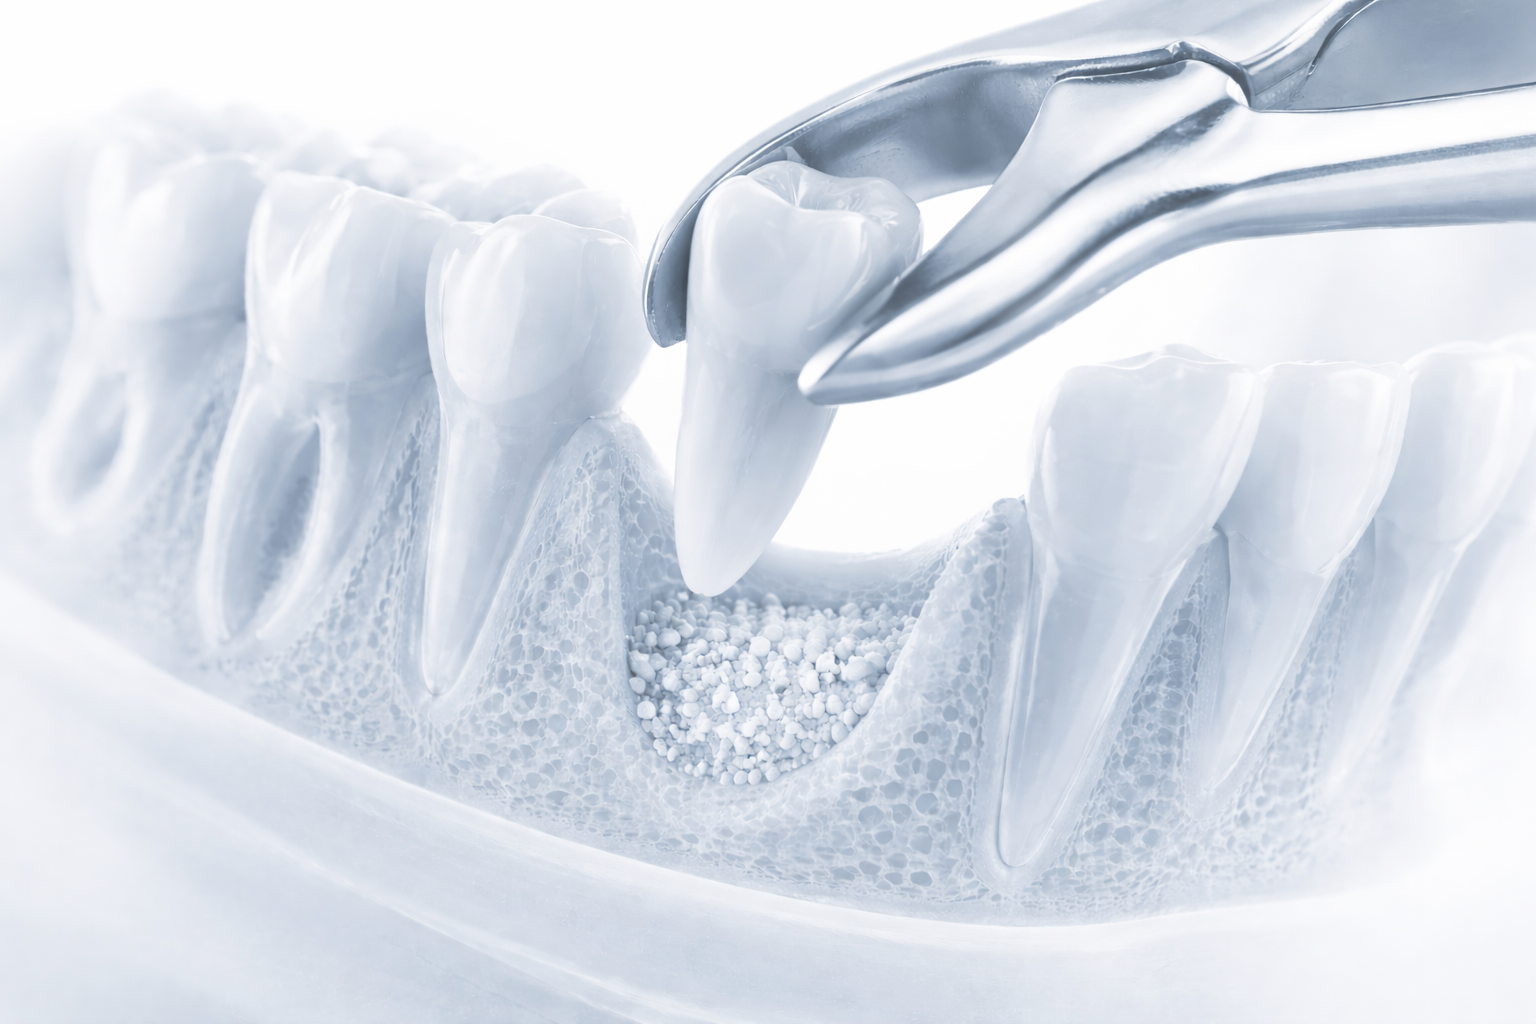

Extraction (if required)

If the tooth is still present, it is removed first. A bone graft may be placed at the same time to preserve the site.